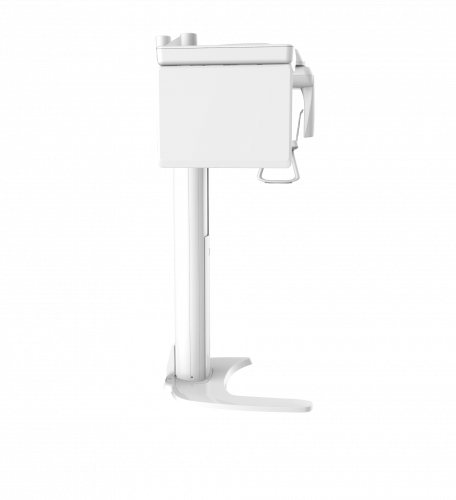

| TYPE | TOP VIEW | FRONT VIEW |

|---|---|---|

|

PaX-i (Pano) |

|

|

|

PaX-i SC (Pano/Scan Ceph) |

|

|